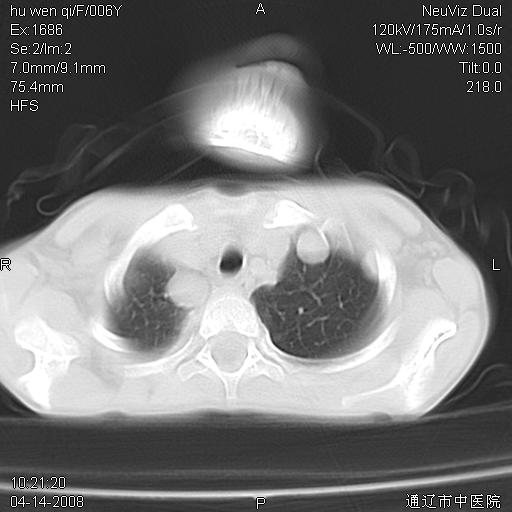

女, 6岁 ,反复咳嗽2周,近两日发热伴右侧胸痛

两肺多发似葡萄状大小不等高密度区,边界清楚,部分见薄壁空洞。左胸壁后方见局限性高密度区,边界清楚,广基与后侧胸壁相连。

考虑:1、金黄色葡萄球肺炎(血源性);

2、左侧包裹性积液;

3、建议严格抗炎治疗后复查。